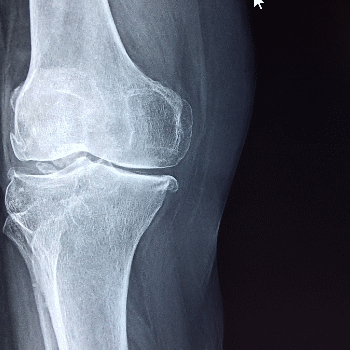

콘드로이친 효능 1. 관절 연골 보호 및 재생

콘드로이친은 관절의 연골을 보호하고 재생을 촉진하는 데 중요한 역할을 합니다. 연골은 관절에서 뼈와 뼈 사이를 부드럽게 움직이도록 돕는 쿠션 역할을 하는 조직입니다. 콘드로이친은 연골 세포를 보호하고, 외부 충격으로부터 연골을 보호하며, 세포외기질의 주요 성분으로서 연골의 구조와 기능을 유지합니다. 이를 통해 관절염 환자의 연골 손상을 줄이고, 새로운 연골 세포의 형성을 촉진하여 관절 건강을 개선합니다.